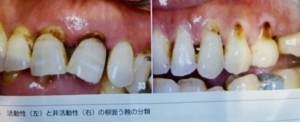

表面性状の分類として探針が容易に挿入できるソフトリージョンは活動性のむし歯であり、挿入できないハードリージョンは非活動性のむし歯とされます。

その中間として、探針は挿入できるが引き抜くさいに抵抗があるレザリーリージョンは非活動、活動性どちらとも言えます。